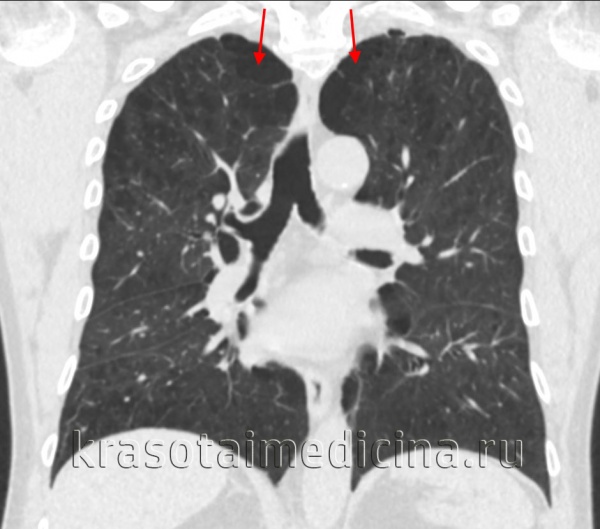

Парасептальные буллы это

Парасептальные буллы это 117 фото